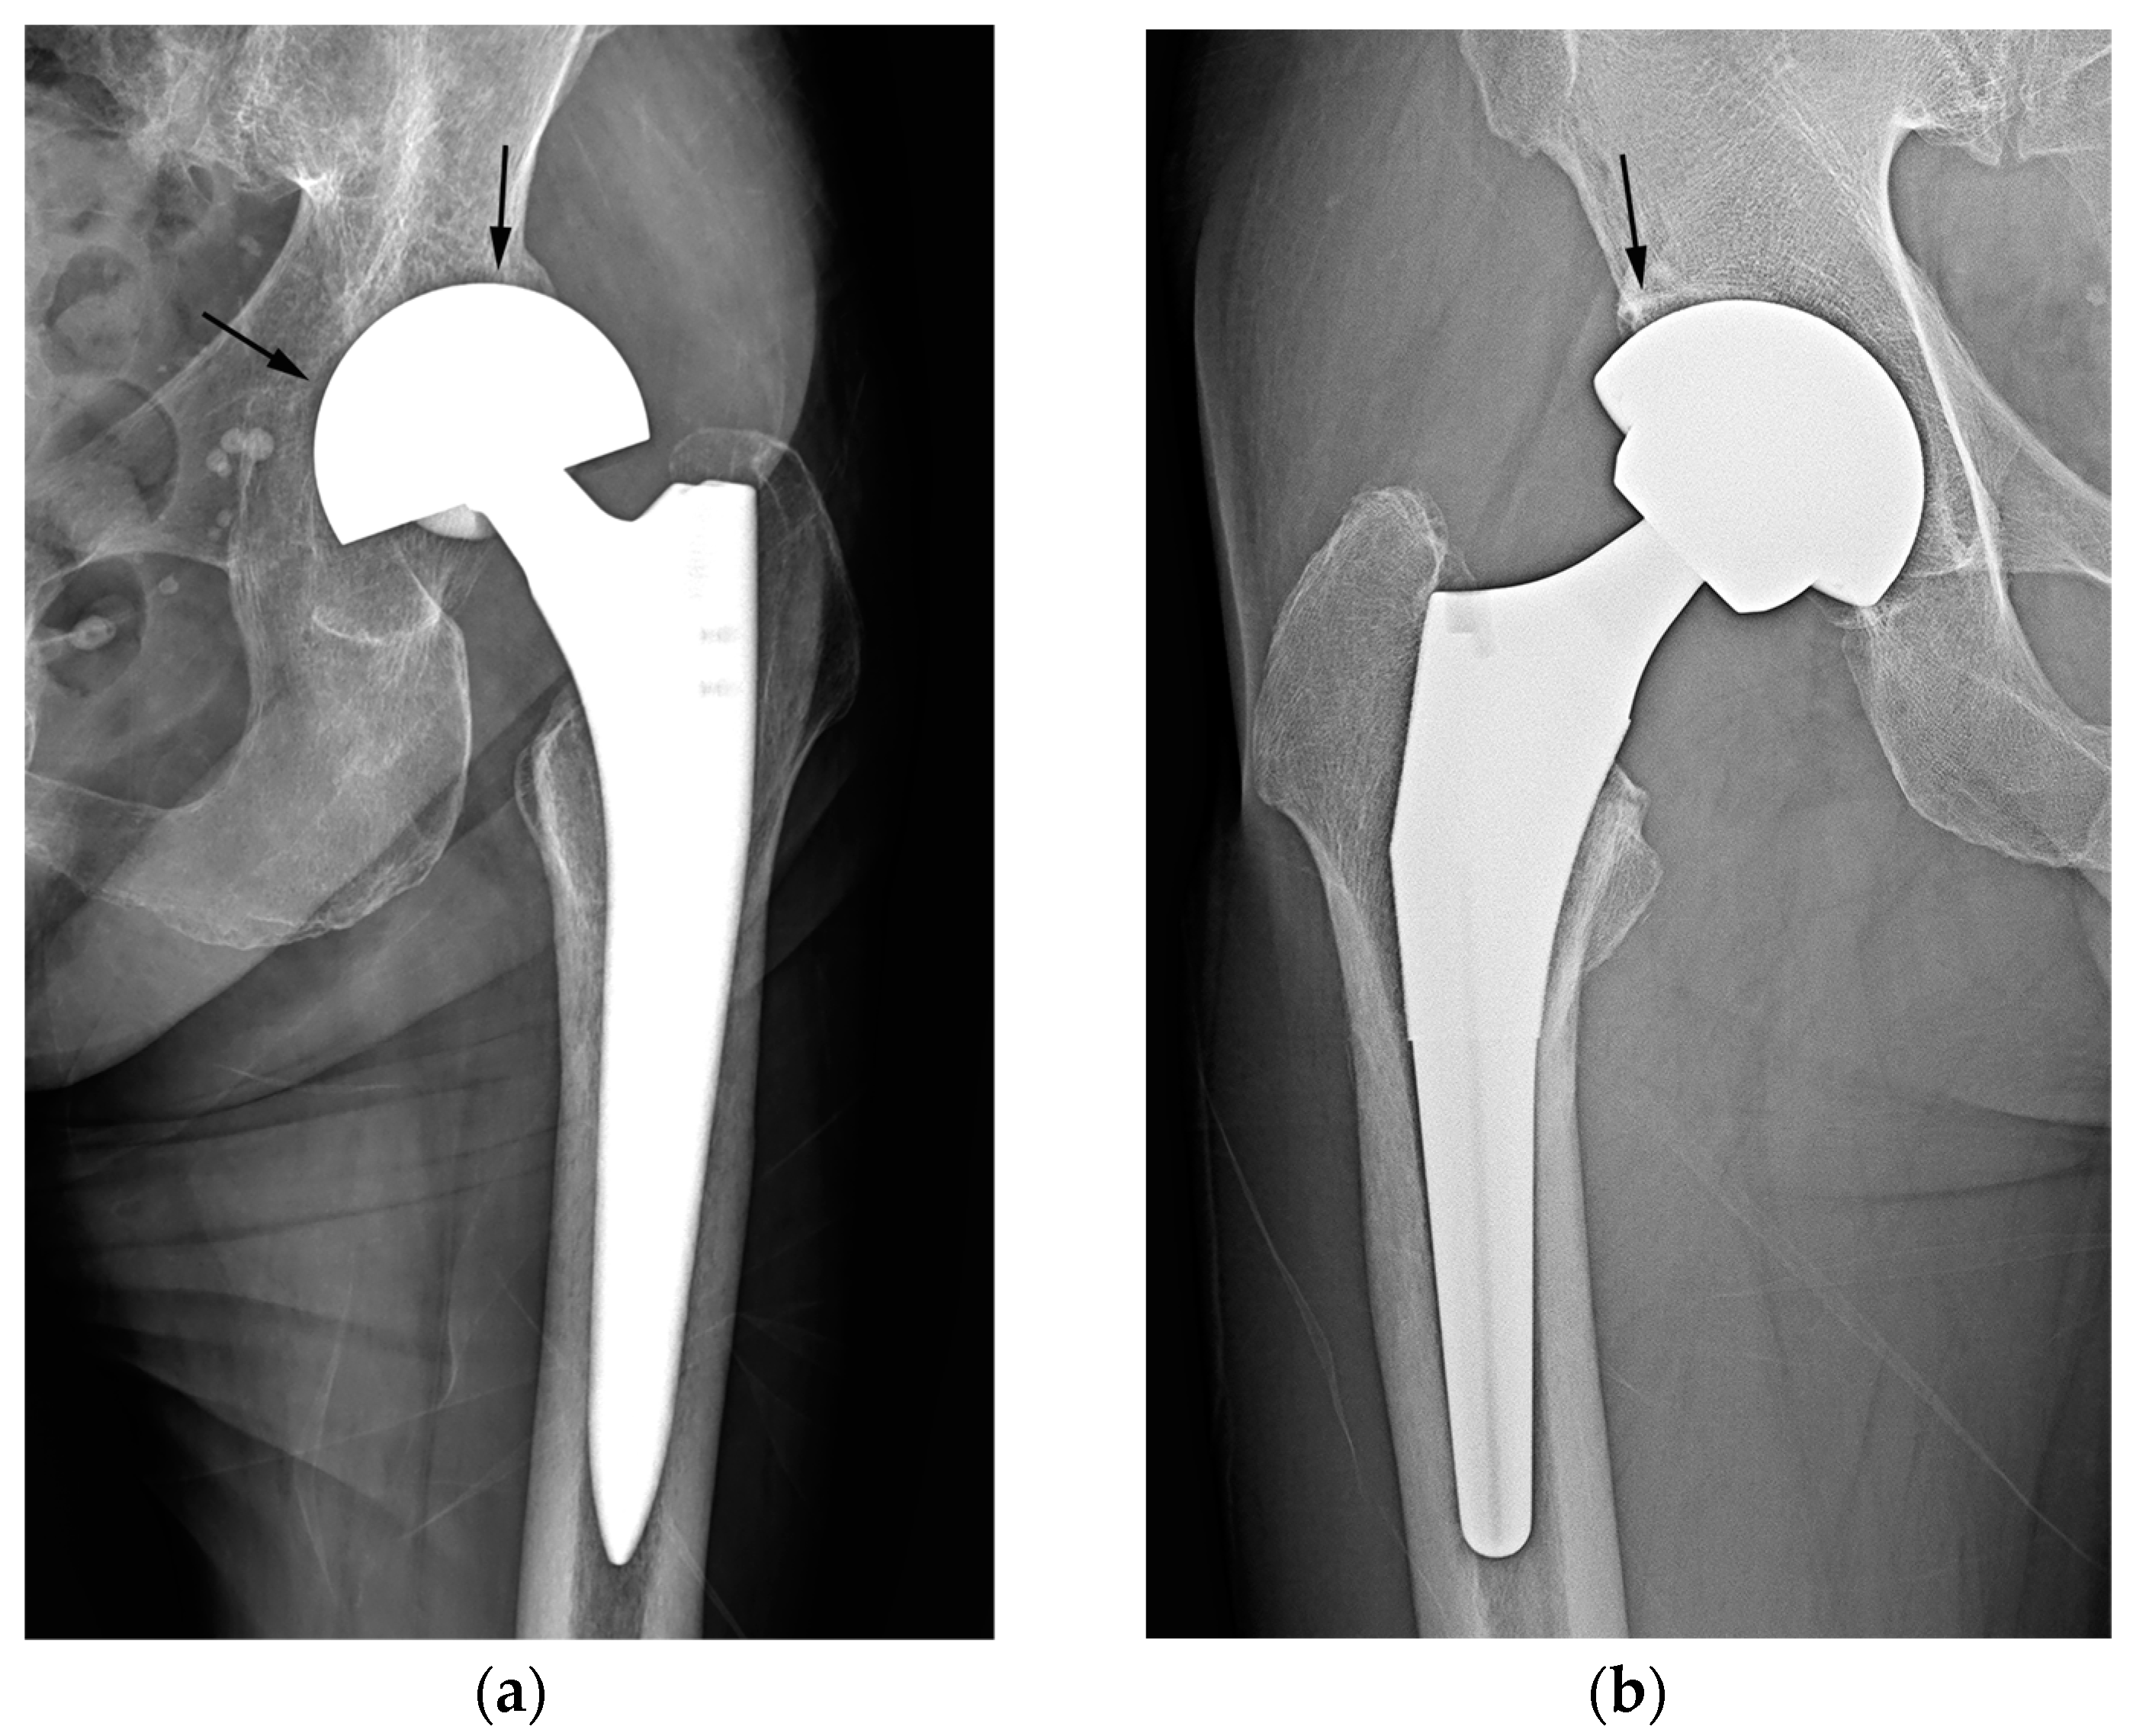

While reviewing the image set, each reader evaluated and recorded the status of acetabular sparing, the texture of the cup–bone interface, and the latitude cut deviation for each item. Acetabular sparing was considered “present” if the joint space and subchondral bone plate area were preserved [2,8]. The texture of the cup–bone interface was categorized as either smooth or textured [8]. The latitude cut deviation was graded in dichotomy based on the results of the first part of the investigation. Specifically, if the latitude cut was made around the equator of the outer circle (i.e., a lower percentage of latitude cut deviation), it was deemed to be “near the equator.” If the latitude cut was made markedly below the equator circle (i.e., with a higher percentage of latitude cut deviation), it was considered to have “deviated from the equator” (Figure 4).

Figure 4.

Simple radiographs of hemiarthroplasty (a) and THA (b). In bipolar hemiarthroplasty (a), the subchondral bone plate of the acetabulum and the adjacent joint space (arrow) are preserved, and the outer surface of the cup appears smooth instead of rough (arrowhead). The chord line of the cup (red line) deviates from the sphere’s equator. In THA (b), the subchondral bone endplate and cartilage space are absent (arrow), and the interface between the cup and bone is smooth, displaying a subtle indentation of the outer spherical contour (arrowhead). The chord line of the cup (red line) closely approaches the equator of the sphere (black line). In both images, the black line represents the equator of the sphere, whereas the red line indicates a chord line connecting the medial and lateral edges of the acetabular cup or bipolar head.